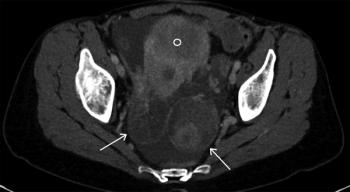

A 27-year-old man presents to his primary care physician, complaining of a palpable nodule in his right testicle. What is your diagnosis?